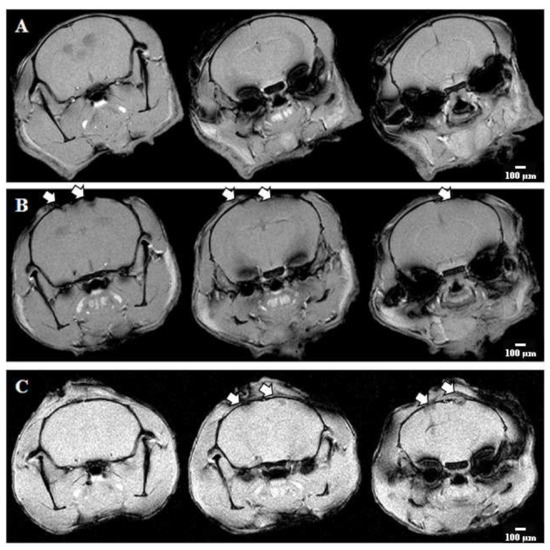

2.1. Studies of the Effect of RIP1 Kinase Blockade on the Functional Activity of Neural Networks in Modeling Ischemic Factors In Vitro

2.2. Effect of RIPK1 Blockade on Resistance of Laboratory Animals to Hypoxic and Ischemic Brain Damage

2.3. Histopathological Evaluation

4.13. Magnetic Resonance Imaging